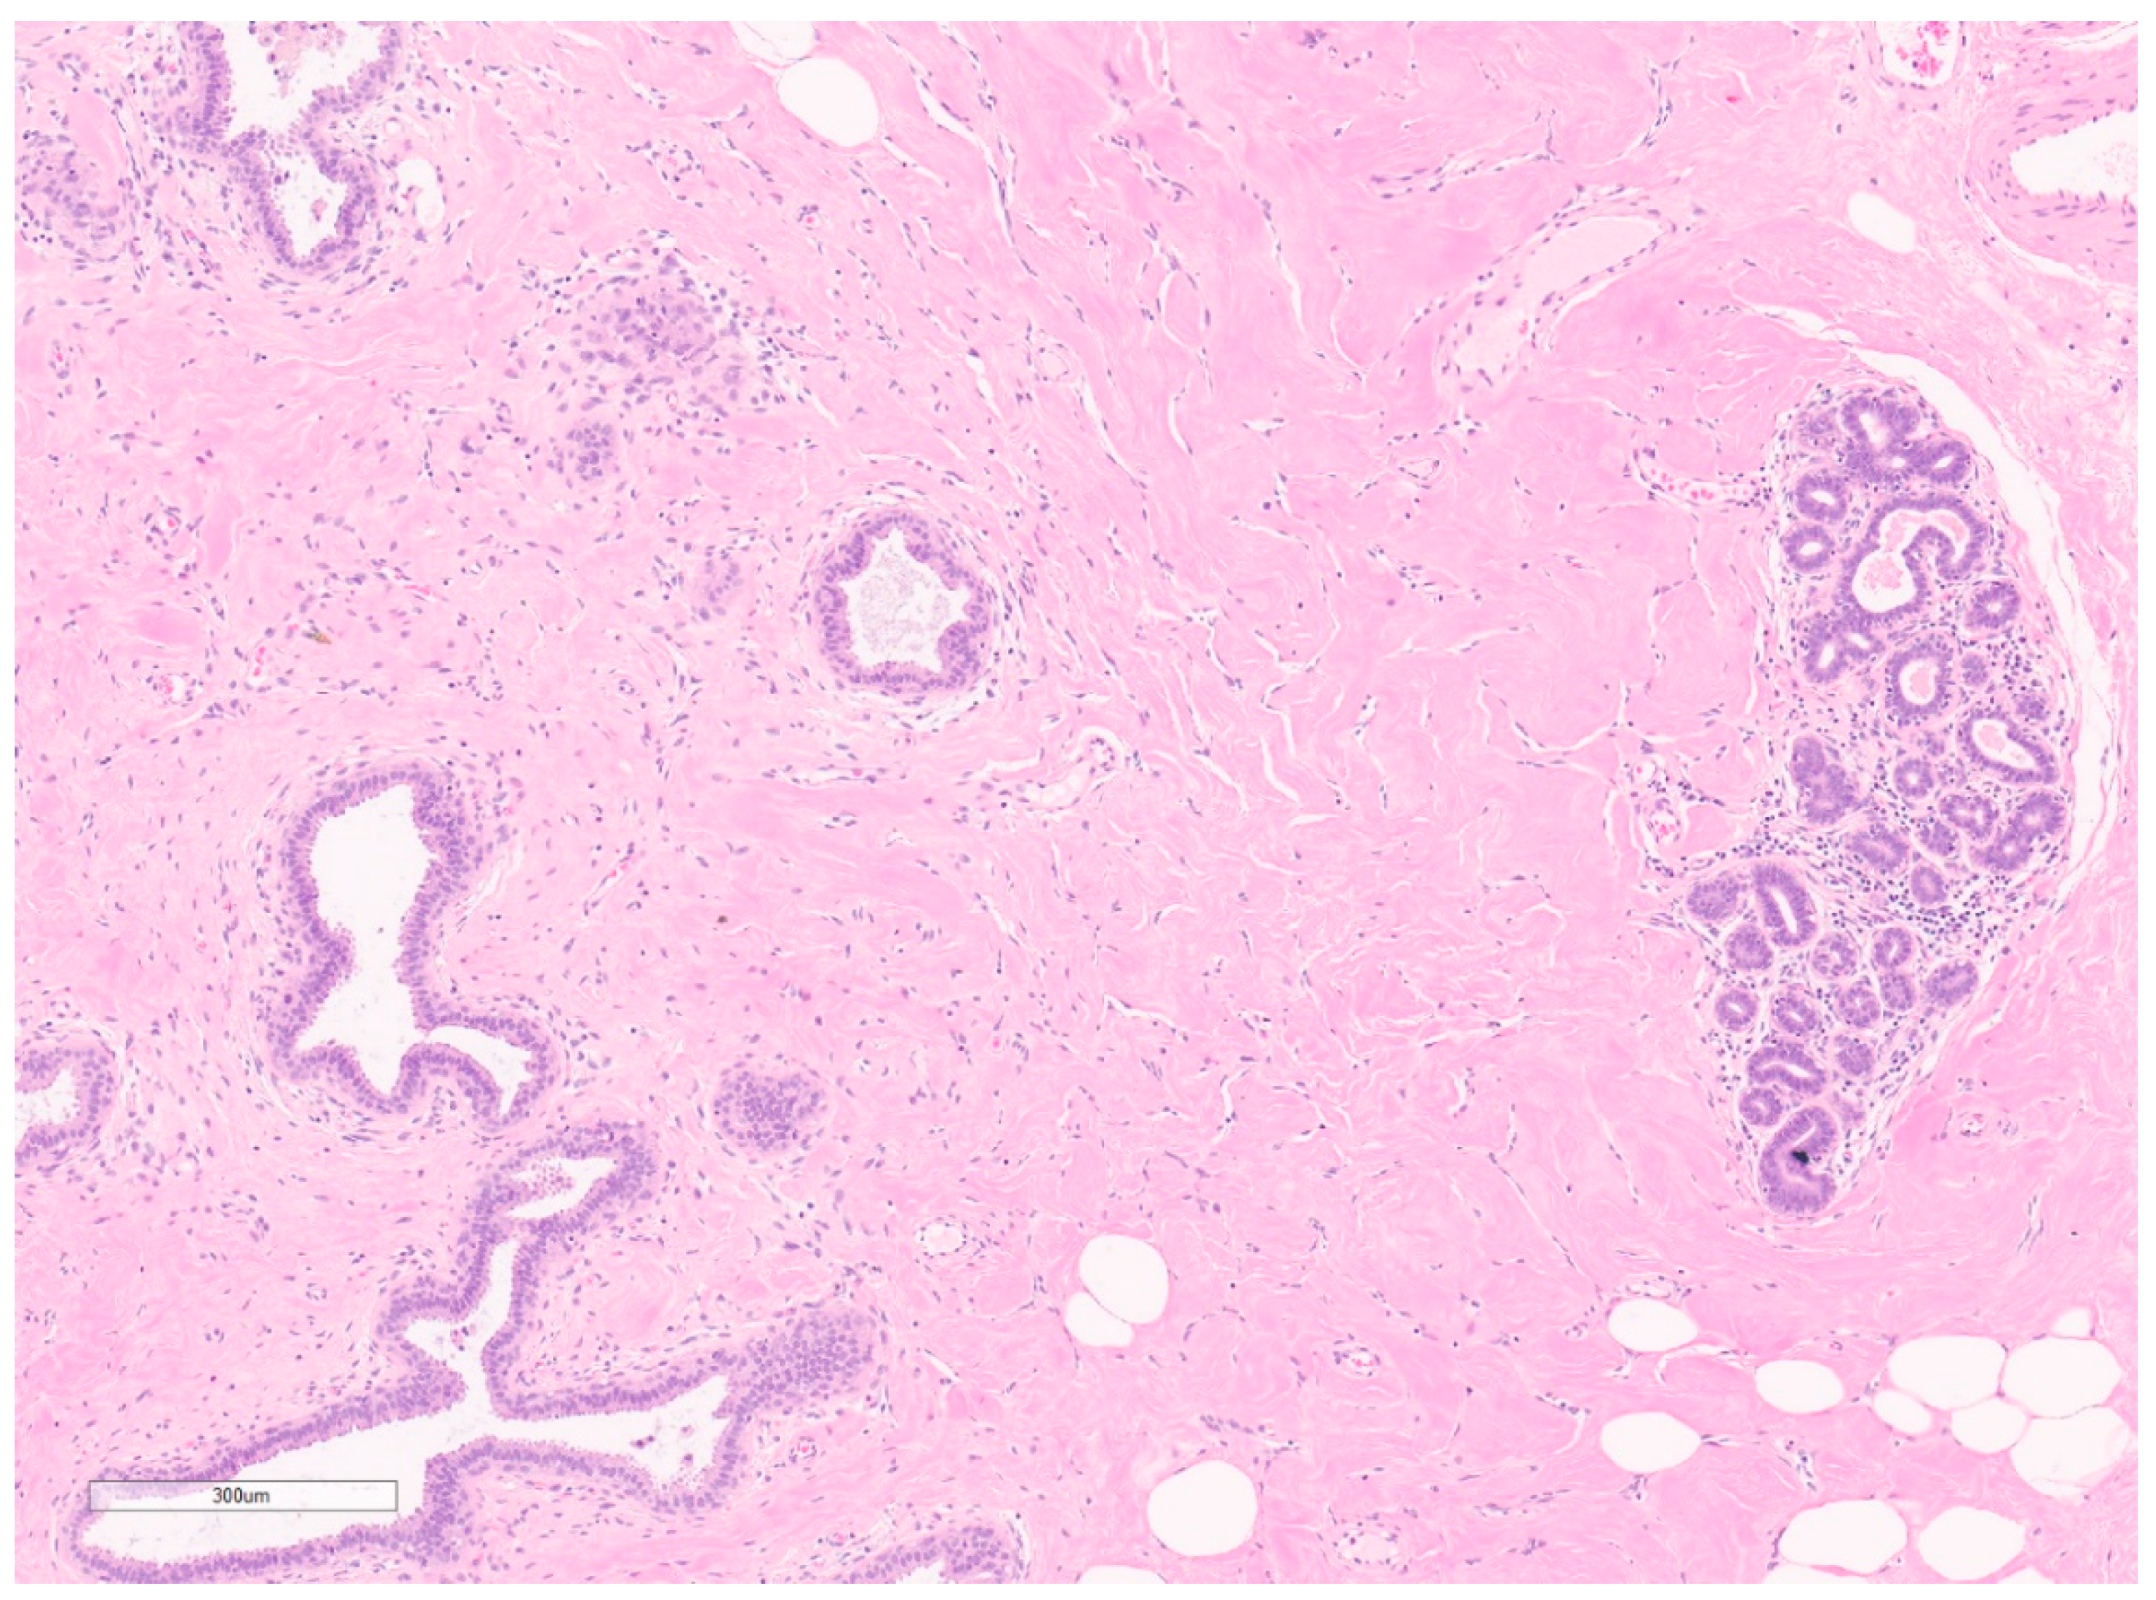

7.1. Pseudoangiomatous Stromal Hyperplasia

7.1.1. Summary of Updates

| Pseudo-angiomatous Stromal Hyperplasia | Pre-menopausal women Risk factors: hormonal exposure including contraceptives, pregnancy, hormone replacement, gynaecomastia | Incidental PASH: occult Nodular PASH: US: hypoechoic, well circumscribed MG: hyperdense, well circumscribed Diffuse: heterogenous, lace-like on US | FNA is often acellular and not useful CNB are adequate—no evidence that it underestimates angiosarcoma as PASH Complex inter-anastomosing channels with spindle cells No erythrocytes In true vascular spaces | Positive: CD34, PR and AR Variably positive: desmin, vimentin, SMA | Most lesions can be observed (no clear surveillance regimen) Surgical excision for PASH > 3 cm, radio-pathologic discordance or serial enlargement No consensus on margins | No malignant transformation Recurrence rates 9–22% |